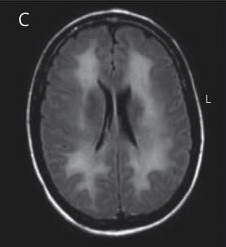

T2 MRI: Supratentorial white matter hyperintensities.

T2-FLAIR MRI: Periventricular white matter hyperintensities sparing U-fibers.